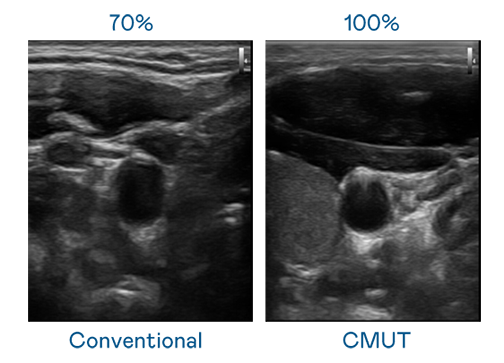

CMUT 技术是一种用电容式微机电元件来产生超音波讯号的技术。与传统 PZT 压电式技术相比,CMUT 频宽增加 30%,更宽频的超音波讯号让影像解析度大幅提升,是实现高影像品质医疗超音波扫描、促进精准医疗发展的关键技术。

超音波影像的解析度高低,首先取决于探头能发出的讯号频宽。EVO CMUT 可提供高清晰的超音波讯号,提供高频宽、高灵敏度、影像纹理细节更高的超音波影像,协助医护人员缩短影像判读时间及利用精准的医疗影像进行诊断。